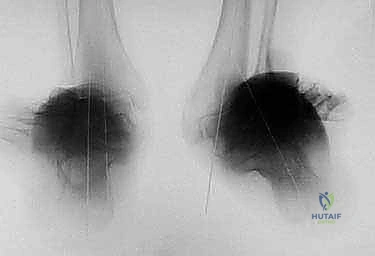

* أشعة سينية طولية للطرفين السفليين أثناء الوقوف (Standing Long-Leg X-rays): هذه هي الصورة الأهم. تسمح للطبيب برؤية محور الساق بالكامل من مفصل الورك، مروراً بالركبة، وصولاً إلى الكاحل.

* الأشعة المقطعية (CT Scan) مع إعادة البناء ثلاثي الأبعاد: ضرورية جداً لتقييم الدوران غير الطبيعي للعظمة (Malrotation) وفهم شكل التشوه في الأبعاد الثلاثة.

* الرنين المغناطيسي (MRI): يُستخدم لتقييم حالة غضاريف مفصل الكاحل، الأربطة، والأوتار المحيطة.

* يتم حساب زوايا المفصل بدقة (مثل LDTA - Lateral Distal Tibial Angle و MDTA - Medial Distal Tibial Angle).